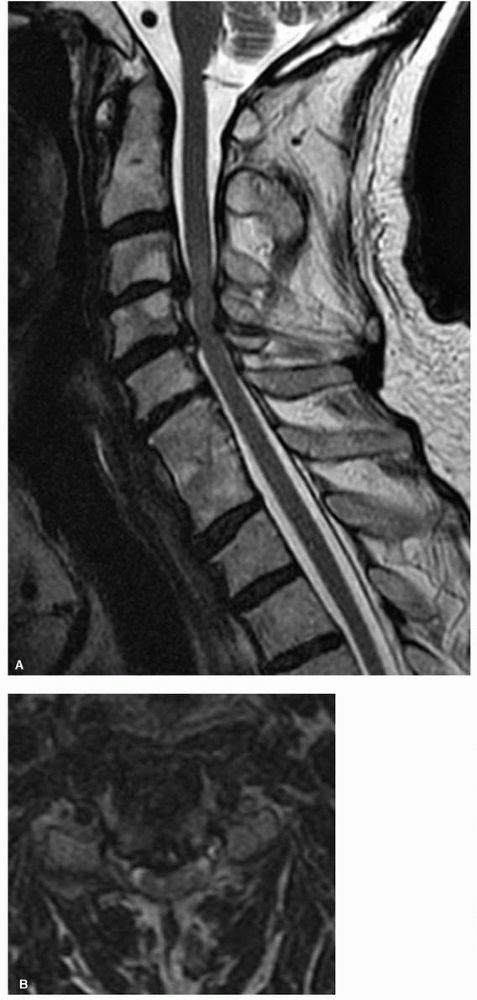

anatomy (Figure 11-6). The disc material and

nerve anatomy can be seen as well as demonstrating pathophysiolocal

effects such as “gliosis” associated with chronic spinal cord

compression. Be careful in assessing the amount of canal compromise on

T2-weighted image because the degree of stenosis can be overestimated.

Under those circumstances a CT or myelogram can be a complimentary

study. Infections, hematomas, and tumors are also much better

visualized by MRI.

FIGURE 11-6. (A)

A sagittal T2-weighted MRI scan of the cervical spine demonstrates chronic disc protrusions at C3-C4 and C4-C5 along with infolding of the ligamentum flavum at those same levels. This is typical of cervical spondylosis and the resultant cord compression has created “gliosis” changes within the cord as illustrated by the increased signal intensity within the cord at the C3-C4 disc level. (B) The corresponding T2 axial images at C3-C4 in the same patient further defines the degree of cord deformity from the compression. |